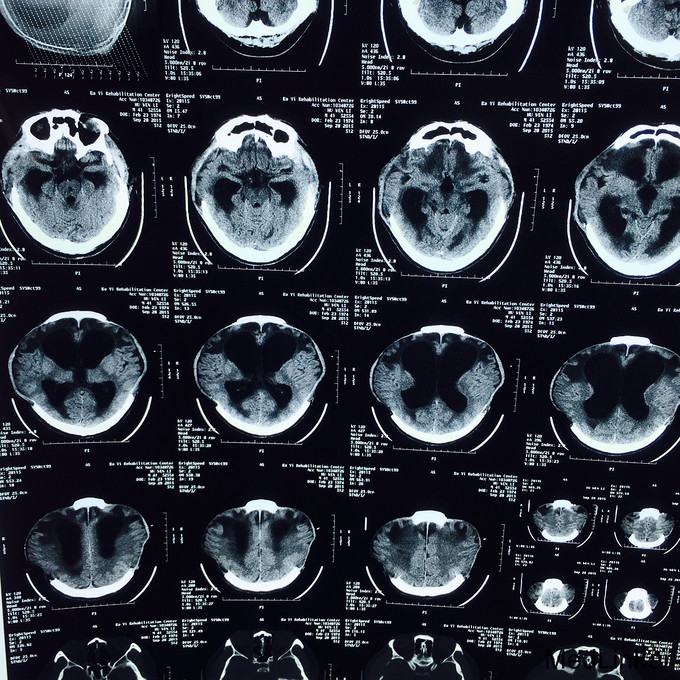

患者,男,41岁,因“脑外伤后意识障碍4月”入院。 现病史: 患者于3月前因高空坠落伤后,出现意识障碍,遂送当地医院,行双侧颅骨去骨瓣减压,血肿清除术,气管切开术;2+月前开始能睁眼,右上肢偶能执行一些简单指令动作,如握手;不能言语,四肢运动功能障碍,左侧为重。大小便障碍,为进一步促醒,康复治疗,遂转本院继续治疗。既往史:既往体健,无重大疾病病史。

入院查体:气管切开,自带鼻饲管,生命体征稳定:脉搏 70次/分,血压121/71mmHg;Glasgow昏迷评分9分,最小意识状态;双侧颅骨缺如;四肢肌张力增高,肌力1-2级,左上肢肘关节活动受限。 辅查:血常规、肝肾功、凝血、电解质、血脂、血糖均正常;头颅MRI(2015.09.17)示:双侧额颞叶及右侧枕顶叶片状低密度影;交通性脑积水;双侧颞额顶骨部分缺如,相邻脑组织膨出,多系术后改变;头颅MRI(2015.09.28)示:与前面的片子比较,变化不大;

诊断:重型颅脑损伤 双侧额叶脑挫裂伤;双侧额颞顶部硬膜下血肿;脑疝形成;最小意识状态。 入院后治疗上积极给以神经营养、床旁康复治疗,高压氧治疗20天促醒;预防肺部感染;预防癫痫发作;

患者病情好转缓慢,2周前强直阵挛发作一次;影像资料提示颅内情况并未明显改善。请神经外科会诊后,建议作脑脊液侧脑室腹腔分流术。对于有脑积水的患者,不排除越早行脑脊液分流术,意识障碍恢复的时间就越短,效果就越好!另外,高压氧治疗方面,怎样发挥出最佳的治疗效果?